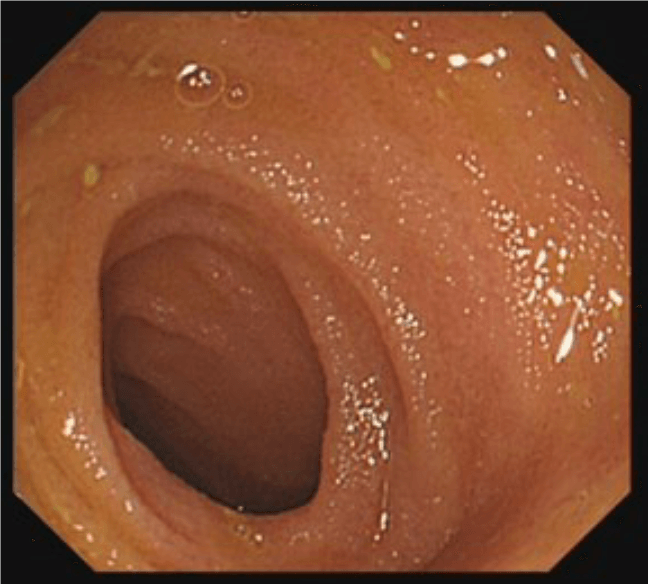

Colonoscopy involves passing a flexible tube (see image alongside) through the anus into the rectum and steering it around the colon. Some images of typical appearances are shown at the bottom of this page (hover over the images for a description).